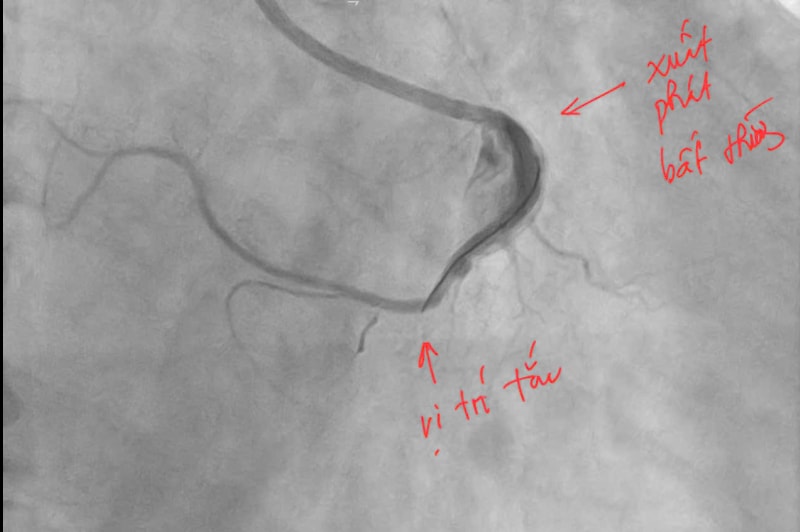

Ngay lập tức, bệnh nhân được kích hoạt quy trình cấp cứu tim mạch và chuyển đến phòng can thiệp mạch vành khẩn cấp. Kết quả chụp mạch vành cho thấy, bệnh nhân bị tắc hoàn toàn động mạch vành phải đoạn 2. Đáng chú ý, động mạch vành phải của người bệnh có vị trí xuất phát bất thường từ xoang vành trái của động mạch chủ – một dạng dị dạng hiếm gặp khiến việc tiếp cận và can thiệp trở nên phức tạp hơn nhiều so với các trường hợp thông thường.

Ê kíp can thiệp do Ths.BS Đinh Danh Trình – Trưởng khoa Tim mạch, Bệnh viện Bãi Cháy cùng các bác sĩ đã thực hiện nhiều thao tác kỹ thuật phức tạp để lái ống thông, đưa dây dẫn và bóng qua vị trí tổn thương. Sau khi tiếp cận được vị trí tắc nghẽn, các bác sĩ tiến hành đặt stent phủ thuốc nhằm tái thông dòng máu nuôi cơ tim.